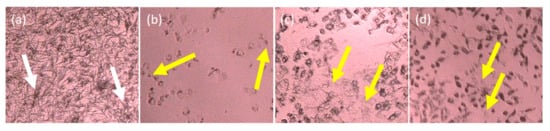

- Goncalves, E.A.; Ventura, C.A.; Yano, T.; Macedo, M.L.R.; Genari, S.C. Morphological and growth alterations in Vero cells transformed by cisplatin. Cell Biol. Int. 2006, 30, 485–494. [Google Scholar] [CrossRef]